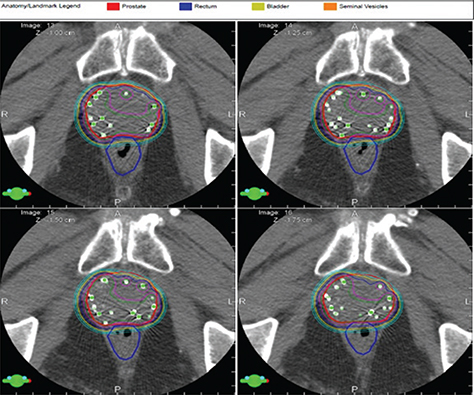

Basic science is also yielding promising results by identifying additional targets for radiation therapy. Prostate cancer cells express different adhesion molecules than normal prostate including integrins; therefore, targeting adhesion molecules in parallel with radiation therapy could provide additive cell kill in prostate cancer patients (4350). Simon and colleagues at the University of Massachusetts demonstrated that high doses of radiation were required to suppress integrin expression (one of the adhesion molecules) in prostate cancer cells and that traditional doses were less effective, implying resistance to traditional radiation therapy and indirectly supporting the utility of higher dose daily treatment that supports an argument for radiation doses similar to modern high dose stereotactic therapy (50). Wang and colleagues demonstrated that Casodex decreased adhesion properties and sensitized prostate cancer cells to radiation therapy. This would suggest that the addition of casodex or surrogate would enhance tumor cell kill with radiation therapy and possibly permit lower doses of radiation therapy to be used and generate similar outcomes. From these series of experiments, cells cloned after surviving radiation therapy have demonstrated resistance to radiation therapy after re-culture. These cells exhibit multiple phenotypic and molecular properties including epithelial-mesenchymal differentiation as well as features consistent with neuroendocrine differentiation (51, 52). Each of these areas have become important opportunities for study and we have pursued these pathways to determine if additional opportunities exist to apply alternate therapy to radiation treatment to increase tumor cell kill. Our group has been able to reverse therapeutic resistance with application of strategic molecular silencing therapy directed towards selected molecular targets (51, 52). Strategies directed to targets associated with survivin and poly (ADP-ribose) polymerise-1 (PARP-1) inhibition exhibit promise in further sensitizing prostate cancer cells to radiation therapy through multiple mechanisms including DNA repair (5357). Extracellular signal related kinases (ERK 1 and ERK 2) appear to be additional targets to sensitize prostate cancer cells to radiation therapy (5153). A series of recent experiments in our group have demonstrated interesting results relative to radiation cell kill in cells that have demonstrated resistance to therapy. Prostate cancer cell line (DU) that survived and regrew post radiation (DI) demonstrated morphologic features consistent transformation into neuroendocrine phenotype expressing neurotensin receptor 1, chromogranin B, and neuron specific enolase, unlike the parent DU cell line. In clonogenic assay, DI cells consistently demonstrate therapeutic resistance in comparison to the parent DU cell. DI cells, ERK1/2 activity is constitutively active in the resistant DI cell, less so in the DU cell. As can be seen in Figure 4, when the resistant DI cell is pre-treated with ERK 1/2 inhibitor U0126, the cells revert to the response to radiation similar to the parent DU cell. This is an exciting finding as it provides an opportunity to study possible mechanisms to therapeutic resistance and pathways to provide additional therapy to mitigate this point.

Fig 4

Figure 4. Combination therapy with radiation and ERK inhibition in neuroendocrine prostate cancer. As seen in the Western blot (a), DI (resistant) cells in a serum free medium display constitutive phosphorylation of PKC and ERK1/2, but not AKT. In figure 4b, clonogenic assay was performed with DI cells treated with and without ERK1/2 inhibitor U0126 (1 μM) 1 hr before exposed to IR with a significant improvement in cell kill when the inhibitor is applied prior to radiation therapy. (Image courtesy of the Department of Radiation Oncology, UMass Chan Medical School and UMass Memorial Health).